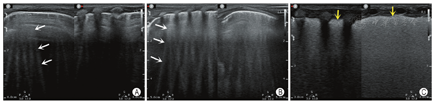

肺点:随着呼吸运动,在实时超声下所见肺滑动存在与肺滑动消失交替点出现的分界点称为肺点(图8A所示)。

肺搏动征:胸膜线与心脏一致的运动,反映肺充气不足,该征象的存在可排除气胸。

平流层征:当肺滑动消失时,在M型超声下,胸膜线下方的颗粒样点状回声被一系列平行线所替代,称平流层征或条形码征(图8B)。

气胸:存在胸膜线与A线,肺滑动征消失,无B线存在,可见肺点,M型表现为平流层征,其诊断流程如图11所示。